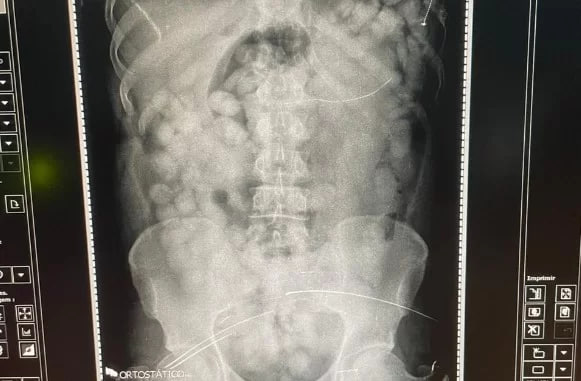

“O raio-x confirmou que havia cerca de 80 cápsulas no estômago, quantidade incomum, o que assustou a equipe policial. Em seguida, o preso foi encaminhado ao PSM, onde começou a expelir a droga ainda nesta manhã de sexta (8), sob custódia de policiais federais”, informou a PF em nota.

Segundo a PF, a quantidade em casos como esse não passa de 40 capsulas.